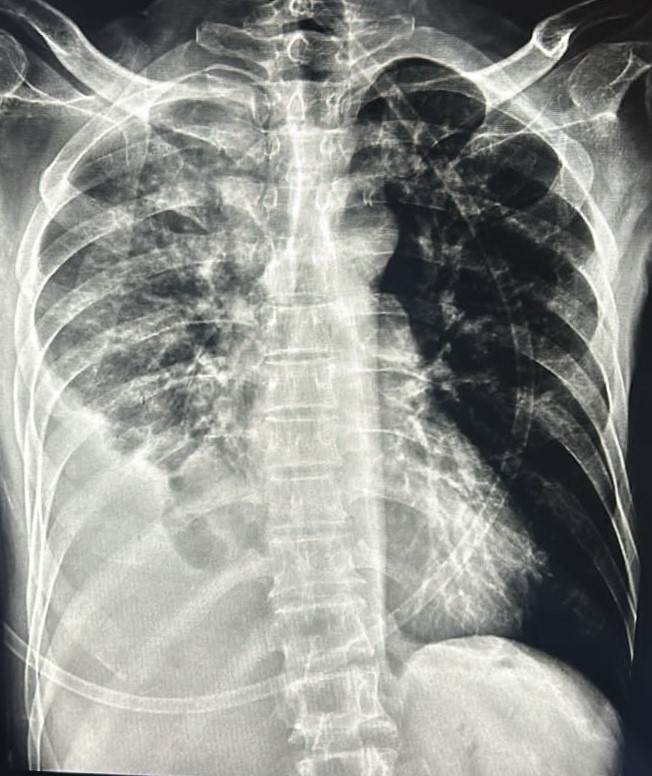

| 338 | IGGMC, Nagpur, Nagpur | P2 | 29-4134 | Rupesh Dongse | Consent taken on Paper | 43 Yrs. |

Provisional Diag : Consolidation

Final Diag : Bilateral Consolidation Community Acquired Pneumonia With Type 1 Respi Failure In Cronic Alcoholic |

Non-TB Case (Confirmed) | Bilateral Consolidation | Abnormality visible on x-ray |